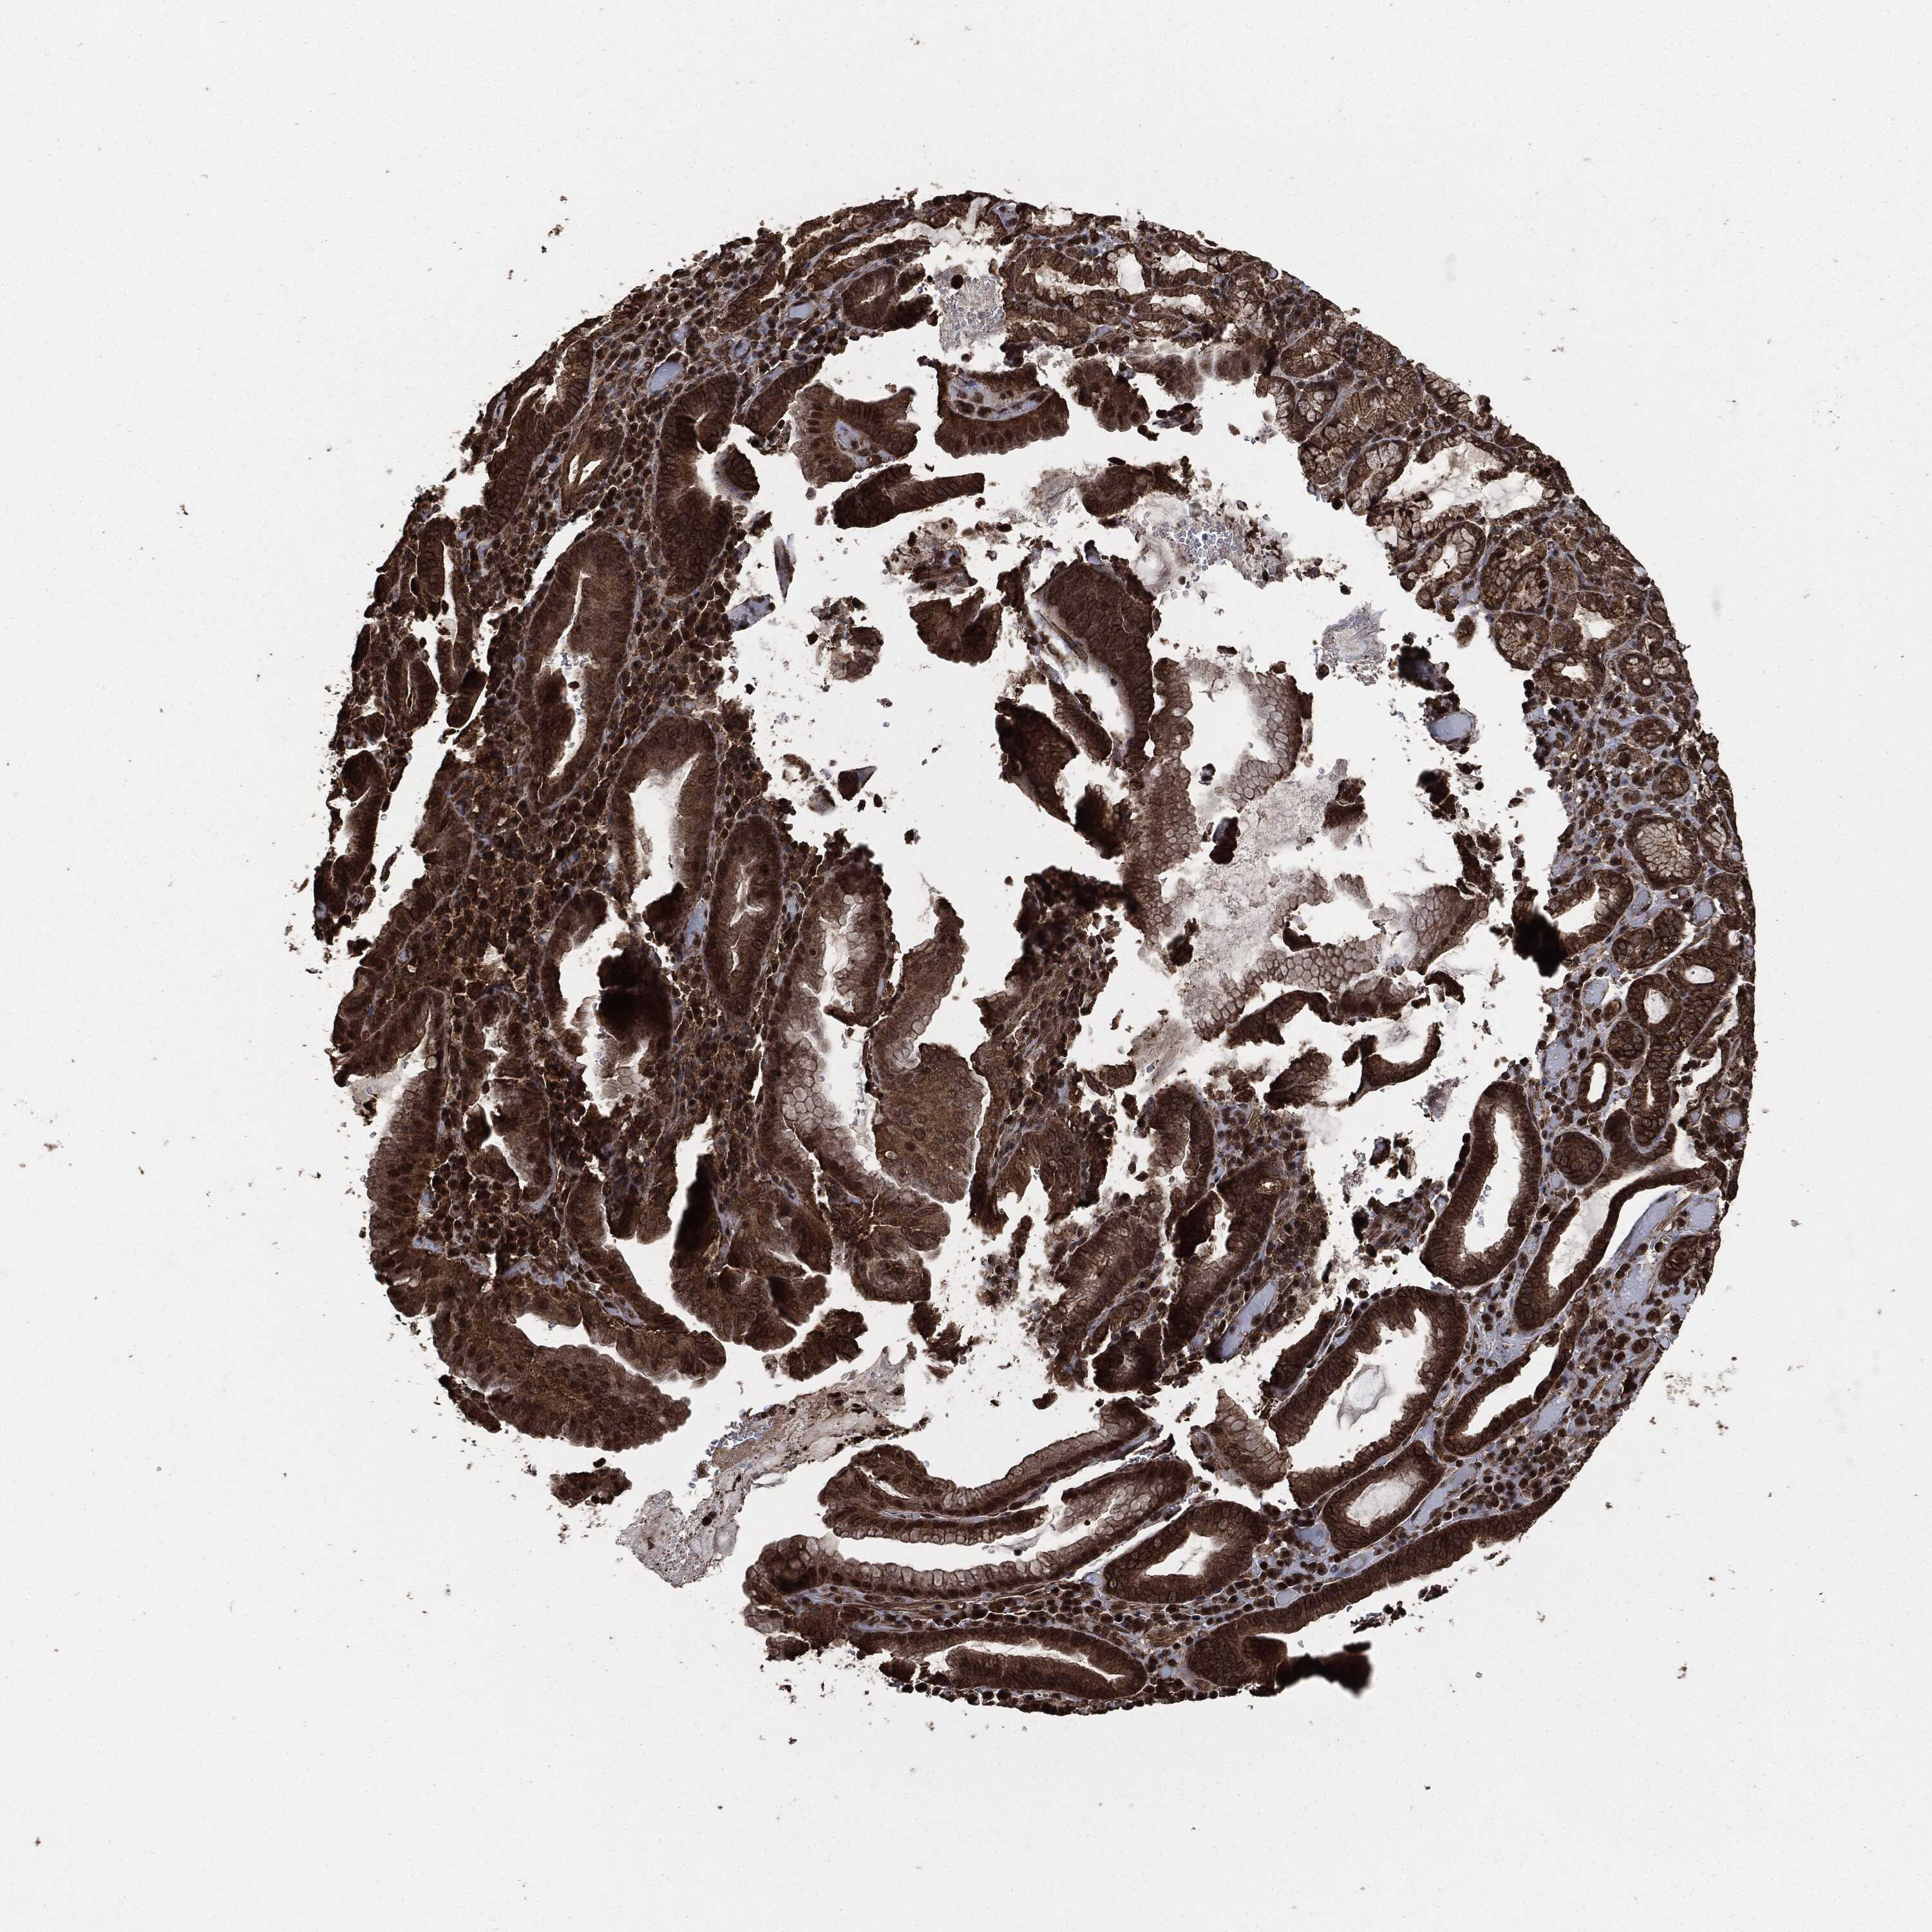

STOMACH CANCER - Protein expressioni

A mouse-over function shows sample information and annotation data. Click on an image to view it in a full screen mode. Samples can be filtered based on level of antibody staining by selecting one or several of the following categories: high, medium, low and not detected. The assay and annotation is described here.

Note that samples used for immunohistochemistry by the Human Protein Atlas do not correspond to samples in the TCGA dataset.

Antibody stainingi

Antibody staining in the annotated cell types in the current human tissue is reported as not detected, low, medium, or high, based on conventional immunohistochemistry profiling in selected tissues. This score is based on the combination of the staining intensity and fraction of stained cells.

Each image is clickable and will lead to virtual microscopy that enables deeper exploration of all samples and also displays staining intensity scores, fraction scores and subcellular localization as well as patient and tissue information for each sample.

HPA049830

CAB002015

CAB080330

CAB080331

CAB080332

Staining

High

Medium

Low

Not detected

Intensity

Strong

Moderate

Weak

Negative

Quantity

>75%

75%-25%

<25%

None

Location

Nuclear

Cytoplasmic/membranous

Cytoplasmic/membranous,nuclear

Adenocarcinoma, NOS

Adenocarcinoma, High grade